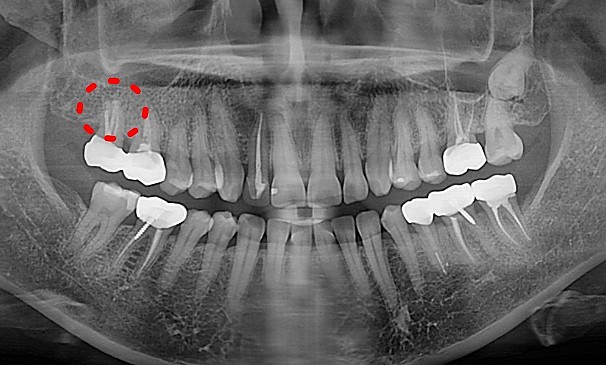

설OO님 전후사진 | 치료 기간 : 1주

치료 전

치료 후